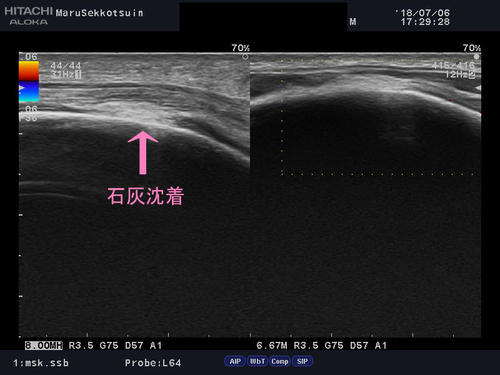

犬の散歩中、リードを不意に引っ張られた後から、肩が上がらなくなった・・・

石灰沈着1.jpg